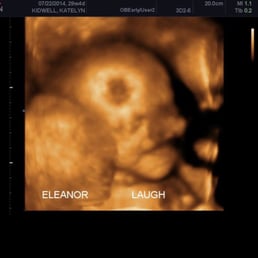

Obstetrics 3d 4d Ultrasound Helvetia Diagnostics Healthcare Center

![]() Tiny Miracles 3d 4d Prenatal Imaging Medical Centers 515 Sanitarium Rd St Helena Ca Phone Number Yelp | ![]() Tiny Miracles 3d 4d Prenatal Imaging Medical Centers 515 Sanitarium Rd St Helena Ca Phone Number Yelp | ![]() Tiny Miracles 3d 4d Prenatal Imaging Medical Centers 515 Sanitarium Rd St Helena Ca Phone Number Yelp |

![]() Tiny Miracles 3d 4d Prenatal Imaging Medical Centers 515 Sanitarium Rd St Helena Ca Phone Number Yelp | ![]() Tiny Miracles 3d 4d Prenatal Imaging Medical Centers 515 Sanitarium Rd St Helena Ca Phone Number Yelp | Tiny Miracles 3d 4d Prenatal Imaging Medical Centers 515 Sanitarium Rd St Helena Ca Phone Number Yelp |

Tiny Miracles 3d 4d Prenatal Imaging Medical Centers 515 Sanitarium Rd St Helena Ca Phone Number Yelp | ![]() Tiny Miracles 3d 4d Prenatal Imaging Medical Centers 515 Sanitarium Rd St Helena Ca Phone Number Yelp | ![]() Tiny Miracles 3d 4d Prenatal Imaging Medical Centers 515 Sanitarium Rd St Helena Ca Phone Number Yelp |

![]() Tiny Miracles 3d 4d Prenatal Imaging Medical Centers 515 Sanitarium Rd St Helena Ca Phone Number Yelp | Tiny Miracles 3d 4d Prenatal Imaging Medical Centers 515 Sanitarium Rd St Helena Ca Phone Number Yelp | Tiny Miracles 3d 4d Prenatal Imaging Medical Centers 515 Sanitarium Rd St Helena Ca Phone Number Yelp |

Tiny Miracles 3d 4d Prenatal Imaging Medical Centers 515 Sanitarium Rd St Helena Ca Phone Number Yelp | ![]() Tiny Miracles 3d 4d Prenatal Imaging Medical Centers 515 Sanitarium Rd St Helena Ca Phone Number Yelp | Tiny Miracles 3d 4d Prenatal Imaging Medical Centers 515 Sanitarium Rd St Helena Ca Phone Number Yelp |